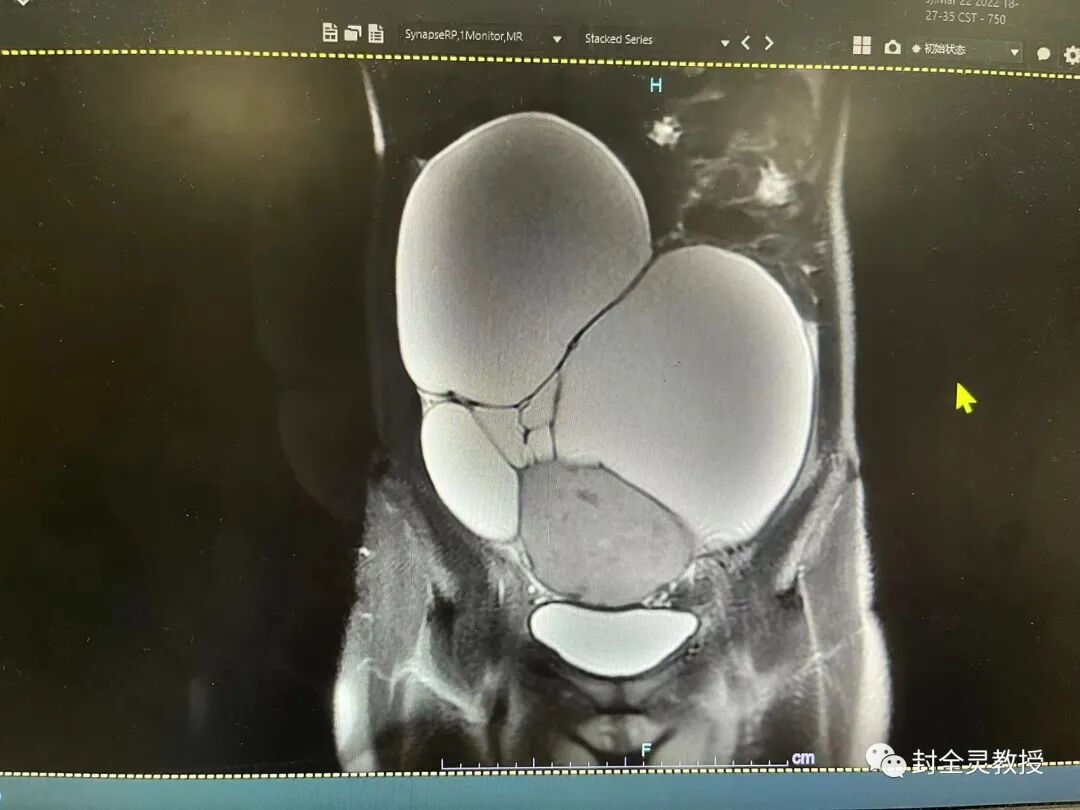

MRI:子宫后倾,形态受压体积较小,结合带完整,宫颈管存在,前后唇无增厚及异常信号;阴道无异常,腹盆腔似可见两团块状混杂长/短T1长T2信号影,T2以不均匀高信号为主、内可见斑片状低信号,并可见多发网状分隔,较大者位于子宫前方,大小约为215.9mm×83..5mm(左右径×前后径X×上下径),较小者位于子宫右后方,大小约为69.8mm×57..3mm(左右径×前后径×上下径),边界清;盆腔及双侧腹股沟未见明确肿大淋巴结。

诊断∶1.腹盆腔囊实性肿块,考虑畸胎瘤可能;2.盆腔积液∶建议结合临床。